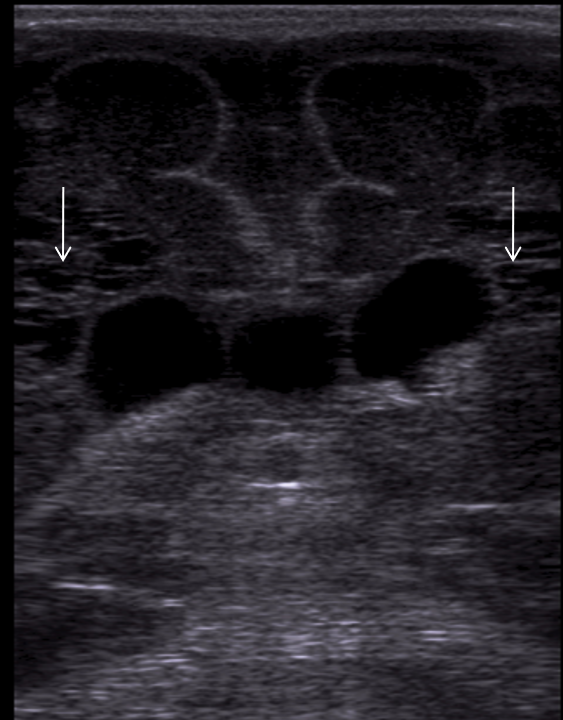

Neonatology Grade 3 PVL 2 Image